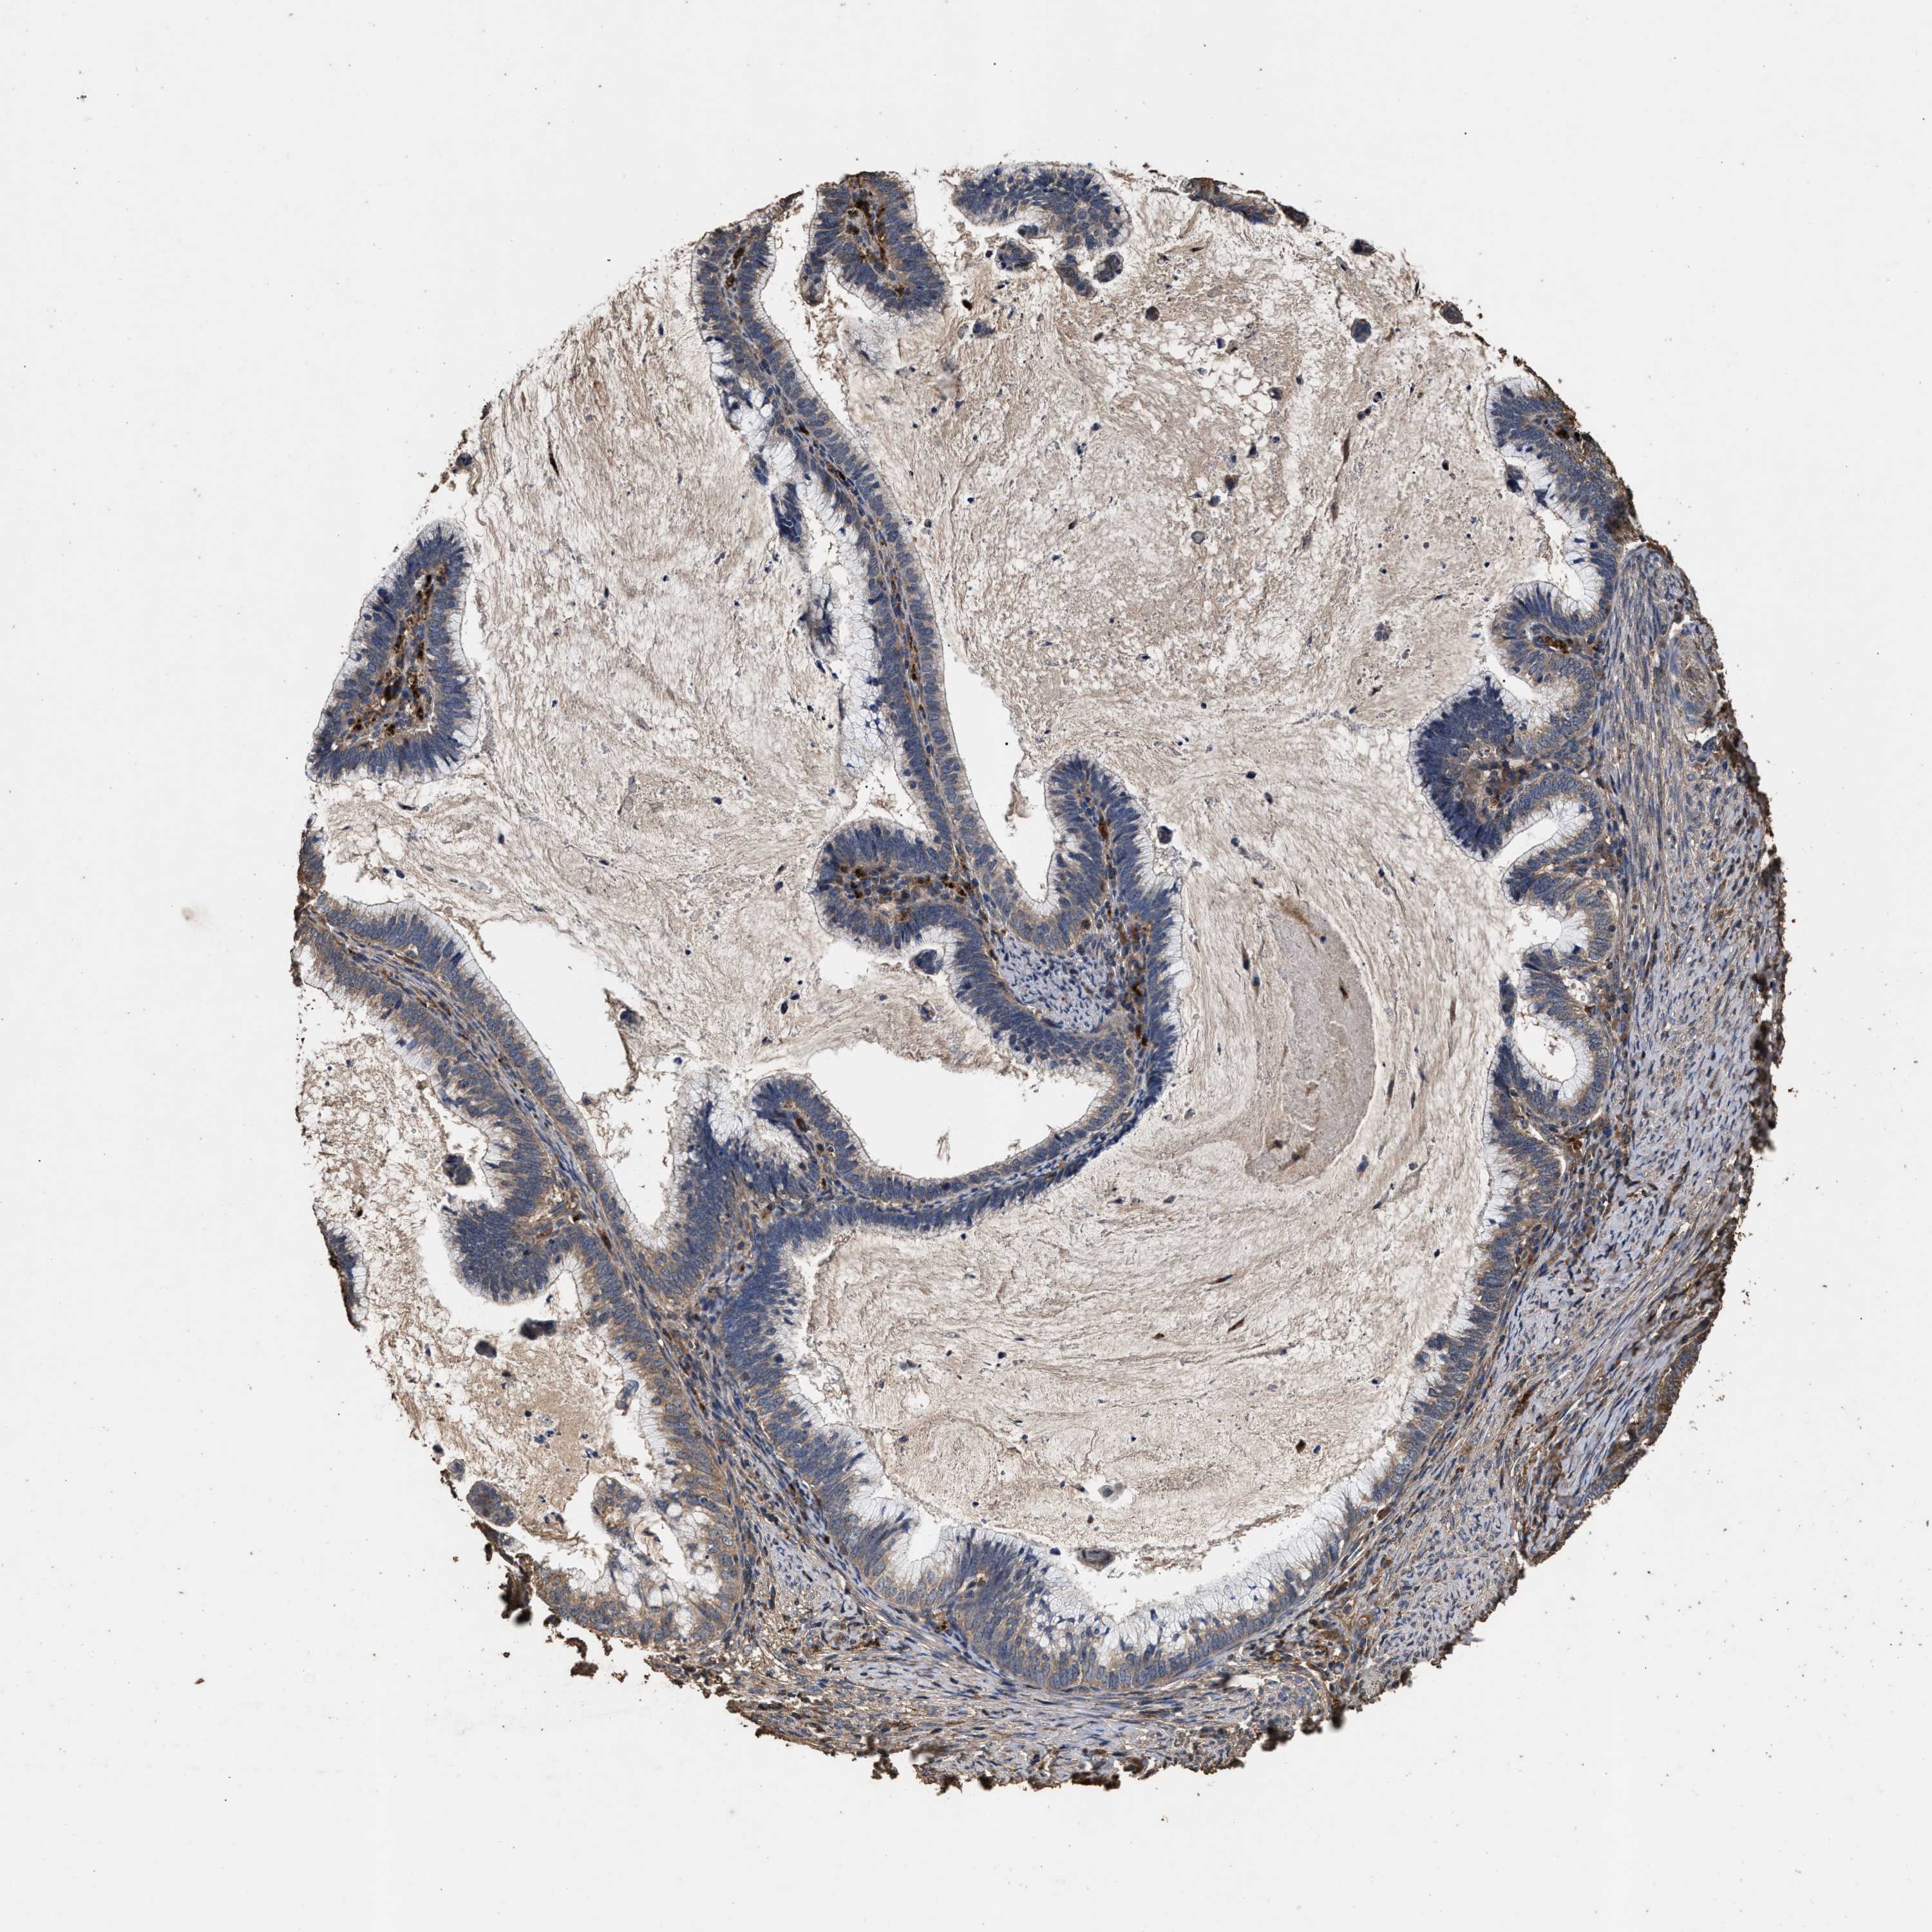

CERVICAL CANCER - Protein expressioni

A mouse-over function shows sample information and annotation data. Click on an image to view it in a full screen mode. Samples can be filtered based on level of antibody staining by selecting one or several of the following categories: high, medium, low and not detected. The assay and annotation is described here.

Note that samples used for immunohistochemistry by the Human Protein Atlas do not correspond to samples in the TCGA dataset.

Antibody stainingi

Antibody staining in the annotated cell types in the current human tissue is reported as not detected, low, medium, or high, based on conventional immunohistochemistry profiling in selected tissues. This score is based on the combination of the staining intensity and fraction of stained cells.

Each image is clickable and will lead to virtual microscopy that enables deeper exploration of all samples and also displays staining intensity scores, fraction scores and subcellular localization as well as patient and tissue information for each sample.

Antibody HPA021176

Antibody HPA021177

Antibody HPA027736

Squamous cell carcinoma, NOS

Adenocarcinoma, NOS